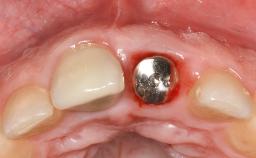

Despite anti-infective surgical treatment, some patients may experience recurrent infection and progressive bone loss requiring additional treatment. Removal of Implant Due to Recurrent Infection describes a conservative approach using an implant retrieval tool without the need for excessive bone removal or use of a trephine.